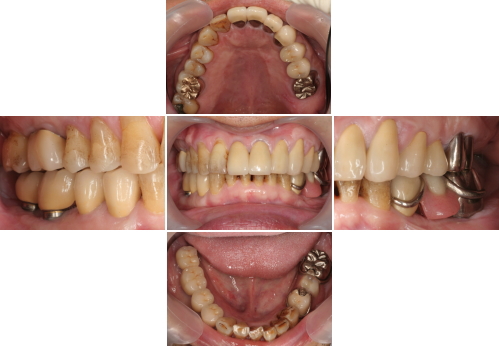

症例5 矯正治療が口腔全体にあたえる影響 64歳 男性

当症例は奥歯の歯ぐきがいつも腫れることが主訴のケースです。

このスライドでも右下の歯肉が腫れています。ひとつ奥の第2大臼歯は数年前に抜歯したそうです。レントゲンで診てみると歯の根が割れて化膿していました。この部分以外の歯肉も時々腫れるそうです。無くした歯も虫歯からではなくて歯周病と言われて抜いたそうです。

左側の上下の歯は、すれ違いを起こしていて噛み合っていません。少し専門的になりますが、前歯と奥歯はお互いに助け合って守りあっています。その関係が壊れてしまうと、奥歯に悪い力がかかり歯が割れたり、歯周病を重症化させてしまいます。このケースはまさにこのケースです。

治療前

治療後